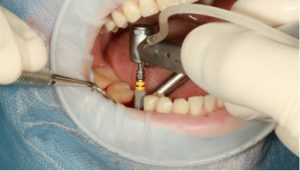

·應用「即刻用种植牙技術」實現當天戴牙

瑞士ITI/瑞士Nobel即刻种植技術